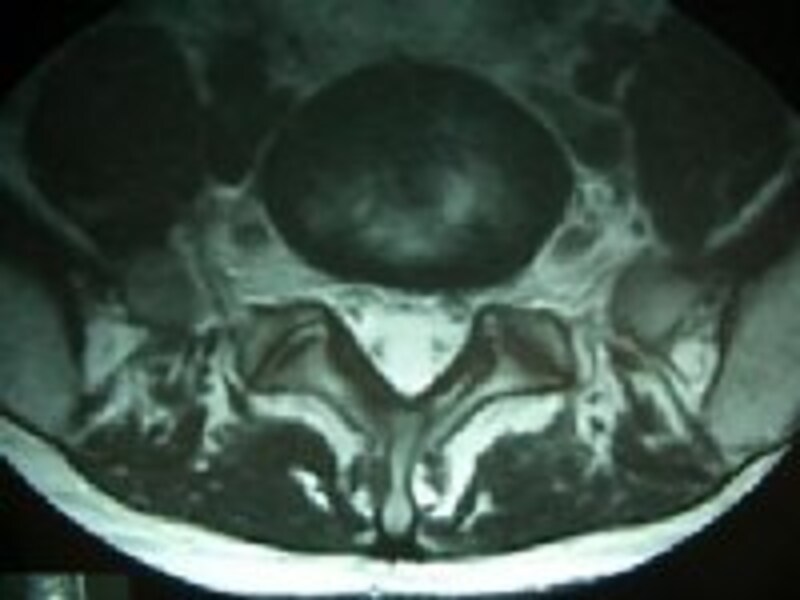

右の画像をご覧ください。腰の状態をよく見るために行われるMRI検査の画像です。(前頁の骨と神経の模型をあわせてごらんください)MRIがどんな検査かということについてはCT、MRIってなあに?へどうぞ)

| 横断面 |